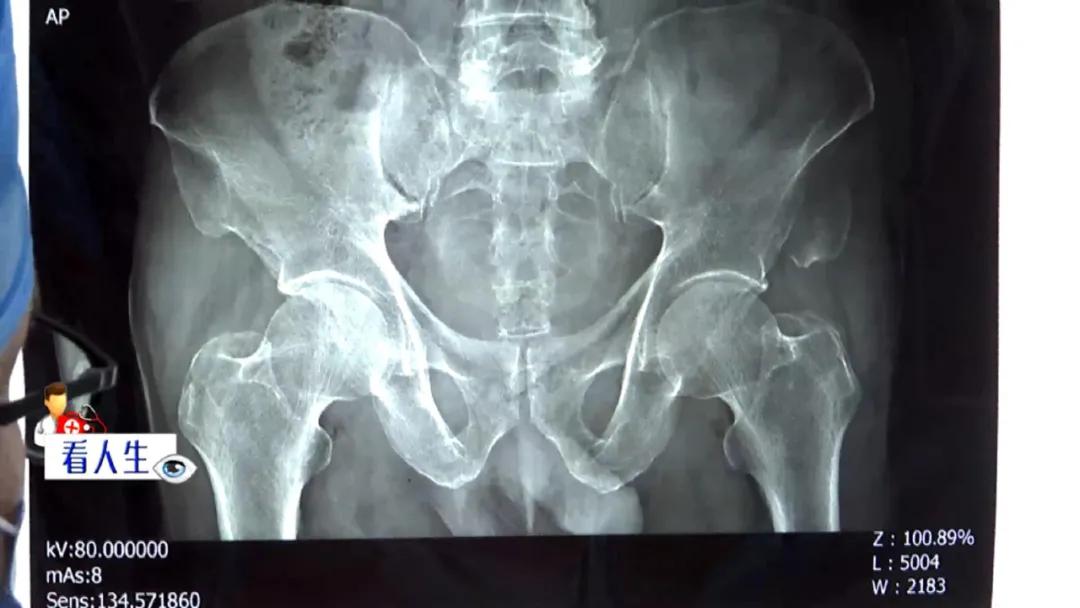

昆医大附一院 急诊外科医生: “这张影像片就看出来了,这一块已经掉下来了。”

肇事方: “您看一下是不是车祸(导致的)还是(陈旧伤),还是什么。”

昆医大附一院 急诊外科医生: “这里的骨折是新的骨折,如果是陈旧的骨折会有骨痂。”

医生解释,骨痂是骨头受伤后愈合过程中形成的伤痂,在影像资料中显示为比骨头断裂处颜色较浅的雾状,是判断是否存在陈旧伤的标准。

昆医大附一院 急诊外科医生: “很明显没有骨痂,就是新的骨折了,这个不需要有什么想法,第一步就是先处理病人好不好?”